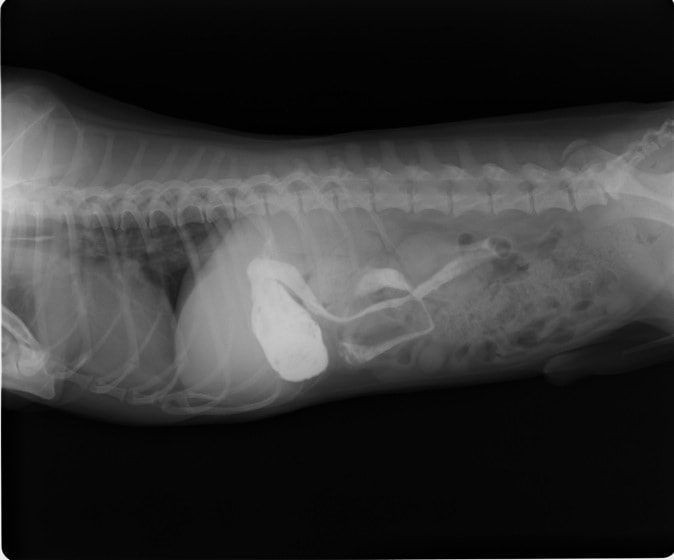

9歳 チワワ 4.8kg

主訴:2日前の夜に桃の種を飲み込んだとのこと。元気・食欲に問題はなく、嘔吐などの消化器症状もみられなかった。誤飲した当日に他院にて催吐処置を試みたが、吐き戻さなかったとのこと。

単純レントゲン検査:明らかな異常所見なし

消化管バリウム造影レントゲン検査:胃内にて異物の存在を疑う異常所見を認めた。

造影直後

内視鏡検査:内視鏡下にて、バスケット鉗子を用いて胃内異物を摘出。

異物内容:桃の種 (約4cm大 写真上)、とうもろこしの芯 (約2.5cm大 写真下)

本症例は、床に落としてしまった桃の種を誤飲していました。動物の体格に対して異物が非常に大きく、開腹手術となる可能性があった症例でした。また、桃の種と一緒に出てきたとうもろこしの芯は、日々のおやつとして与えていたものということでした。とうもろこしの芯は非常に硬く、小さく切って与えても消化されず、長期間胃内に残ってしまうことや腸閉塞の原因となる為、注意が必要です。